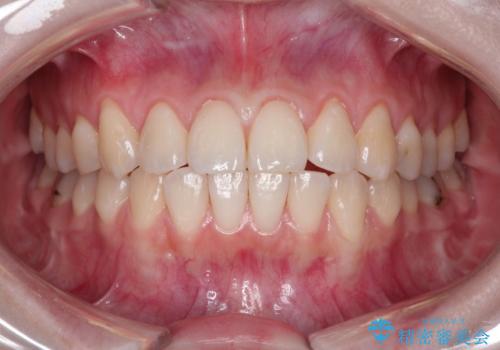

前歯の歯肉退縮 歯周形成外科(歯冠側移動術)

- 上顎左側側切歯の歯肉退縮を主訴に来院されました。

生活に支障はないが審美的要求が強く歯肉形成外科(歯冠側移動術)を行うこととしました。

根面被覆術には結合組織を用いる場合もありますが、今回のケースでは、角化歯肉が十分あり、審美性の要件が強いため、隣在歯との調和が取りやすい歯冠側移動術のみで対応しております。